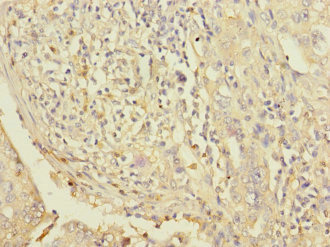

應用范圍:ELISA, IHC

Application Recommended Dilution IHC 1:20-1:200 -